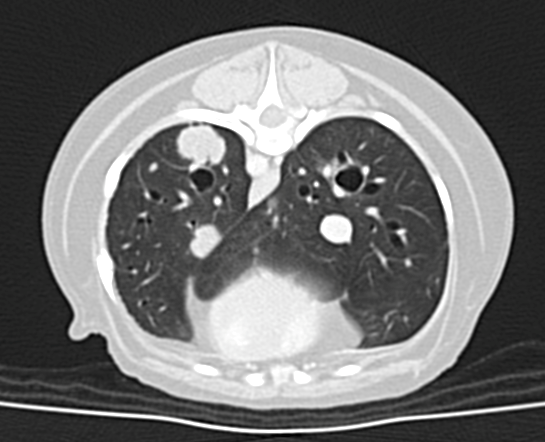

⑥ CT検査         (図4 CT画像:乳腺腫瘍の肺転移)

–レントゲン検査/超音波検査より、詳細に遠隔転移の有無を調べられます。

図4 CT画像:乳腺腫瘍の肺転移